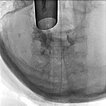

Damit Entschluss zur Sklerosierung der Anteile der venösen Malformation, die direkt im Bereich des Larynx die Atemwege einengen. In der biplanaren Angiographie wird mit dem starren Laryngoskop zunächst die Situation dargestellt (linkes Bild). Im Endolarynx sind die Stimmlippen durch supraglottische Ausläufer der venösen Malformation vollständig verdeckt und nicht mehr sichtbar.

Zur Sklerosierung wird durch das starre Laryngoskop mittels einer Fasszange eine Butterflynadel in die venöse Malformation zur Punktion vorgeschoben. Nach Aspiration von Blut wird hier Kontrastmittel injiziert zur Sicherung der Nadellage in der venösen Malformation vor Einspritzung des Sklerosierungsmittels.

Die Kontrolldurchleuchtung nach Kontrastmittelinjektion zeigt eine korrekte Nadellage in der venösen Malformation ohne Abstrom über eine größere Kommunikationsvene. Damit kann die venöse Malformation über diese Position gut sklerosiert werden.